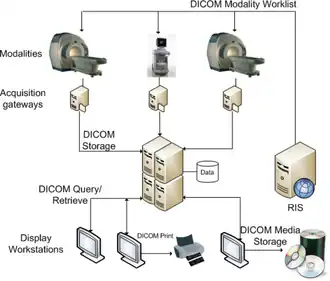

The digital age’s impact on radiology resulted in a large influx of data that needed to be managed. To combat this, the field of information technology was incorporated with technology such as Radiology Information System (RIS)[7] and Hospital Information System (HIS). These systems would work in tandem with PACS and other imaging technology to streamline the patient data management, as shown in the figure to the right.[8]